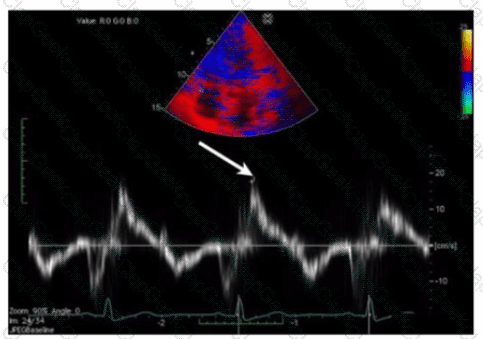

Which patient positioning is best for obtaining the waveform seen in this image obtained by a non-imaging transducer?